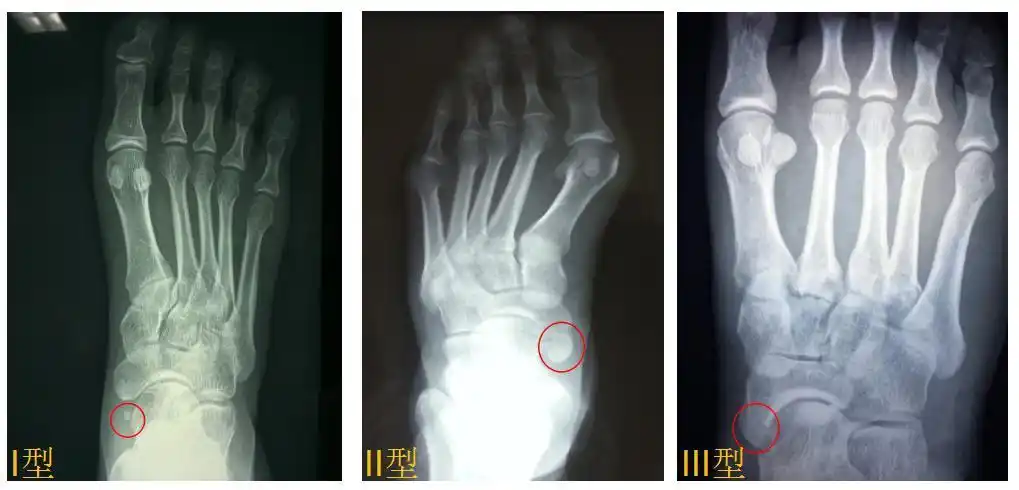

卫生社团足痛隆起畸形当心副舟骨疼痛综合征在作怪

足的副舟骨是什么梗看完这篇文章就全明白了

足舟骨科普篇